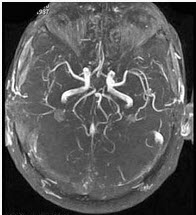

男,35岁,头痛半年加重1周,左侧肢体无力,影像检查如图所示,最可能的诊断为()

A:脑血管畸形

B:脑梗死

C:脑出血

D:脑炎

E:脑静脉性血栓